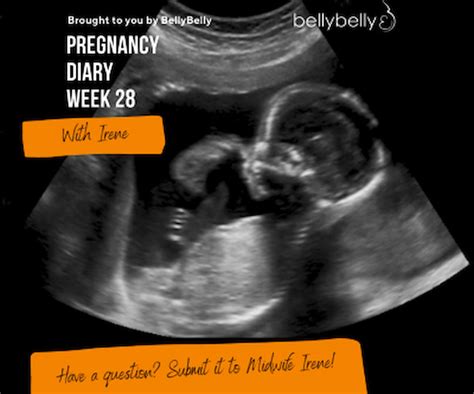

Reaching the third trimester is a significant milestone in any pregnancy journey, and hitting the 28 weeks pregnant belly mark often feels like a turning point. At this stage, your baby is growing rapidly, your body is undergoing visible changes, and the anticipation for your little one’s arrival is starting to feel very real. Many expectant mothers notice that their belly becomes the main attraction during this time, often accompanied by new physical sensations and emotional shifts as you enter the final stretch of gestation.

At 28 weeks, your baby is roughly the size of an eggplant or a large cauliflower. As they gain weight and begin to fill out, your uterus expands upward, which is why your 28 weeks pregnant belly might start to feel more prominent and perhaps a bit tighter. The top of your uterus is now about three to four inches above your belly button. This expansion creates significant pressure on your surrounding organs, which is a common reason for the shortness of breath or frequent bathroom trips you may be experiencing.